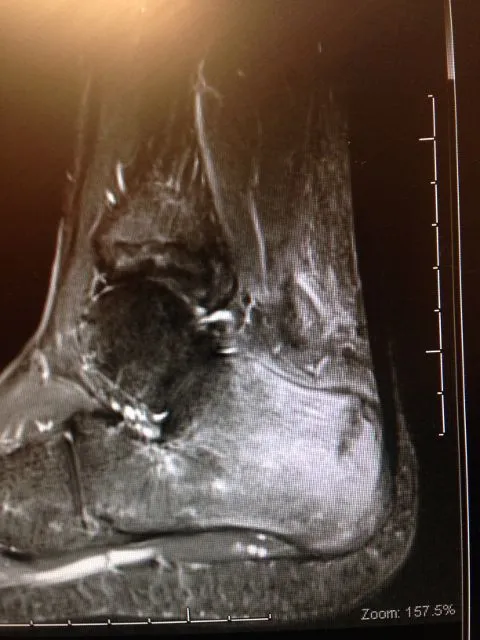

MRI imaging is excellent for diagnosing stress fractures. A T1 weighted image will show normal bone in a white color and edema and/or fracture lines in gray to black color (below left). T2 weighted imaged are the opposite and will show bone black and any fluid like swelling within the bone or throught a fracture as white (below right).